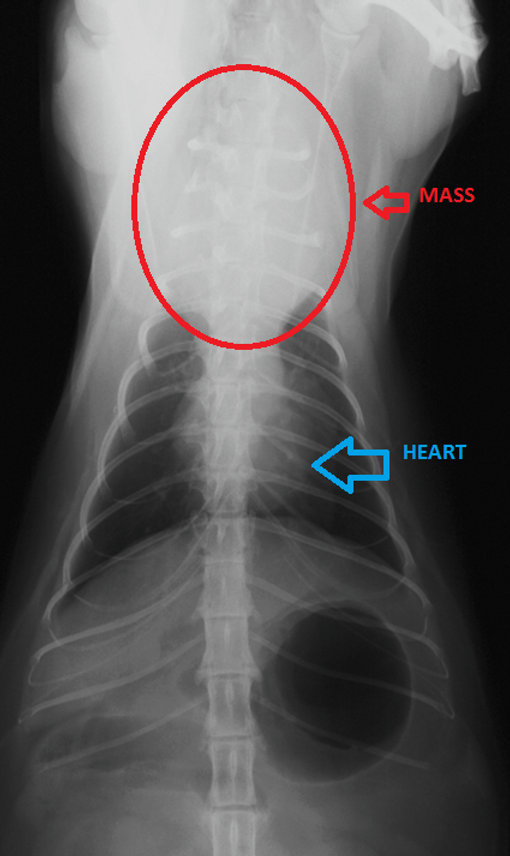

Mediastinal Lymphoma In Cats Symptoms When lymphocytes form in the chest this is referred to as disseminated lymphoma. Clinical signs of lymphoma in the gastrointestinal tract include weight loss vomiting diarrhea and often either a decreased or increased appetite. This type of lymphoma creates a tumor in a part of the chest cavity between the lungs called the mediastinum.

It often affects young cats and cats with FeLV. Pets suffering from this lymphoma may cough. Physical exam findings may be normal.